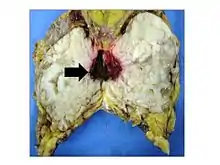

Phyllodes tumors may be considered benign, borderline, or malignant depending upon their histological features, including stromal cellularity, infiltration of the epithelial-stromal interface, and mitotic activity.[15] Due to their propensity to metastasize and grow quickly, almost all phyllodes tumors are regarded as having malignant potential and treated accordingly.[15] A large case series from the M.D. Anderson Cancer Centre reported the incidence of each type of phyllodes tumor as benign (58%), borderline (12%), and malignant (30%).[16]

.jpg.webp)

Malignant phyllodes tumors can behave similarly to sarcomas leading to development of blood-borne metastases.[16] Approximately 10% of phyllodes tumor develop distant metastases and this occurrence is higher (20%) in patients with histological-identified malignant tumors.[16] The most common site for distant metastases include the lung, bone, and abdominal viscera.[17] In more insidious cases, the parotid region has also been described in literature.[18]